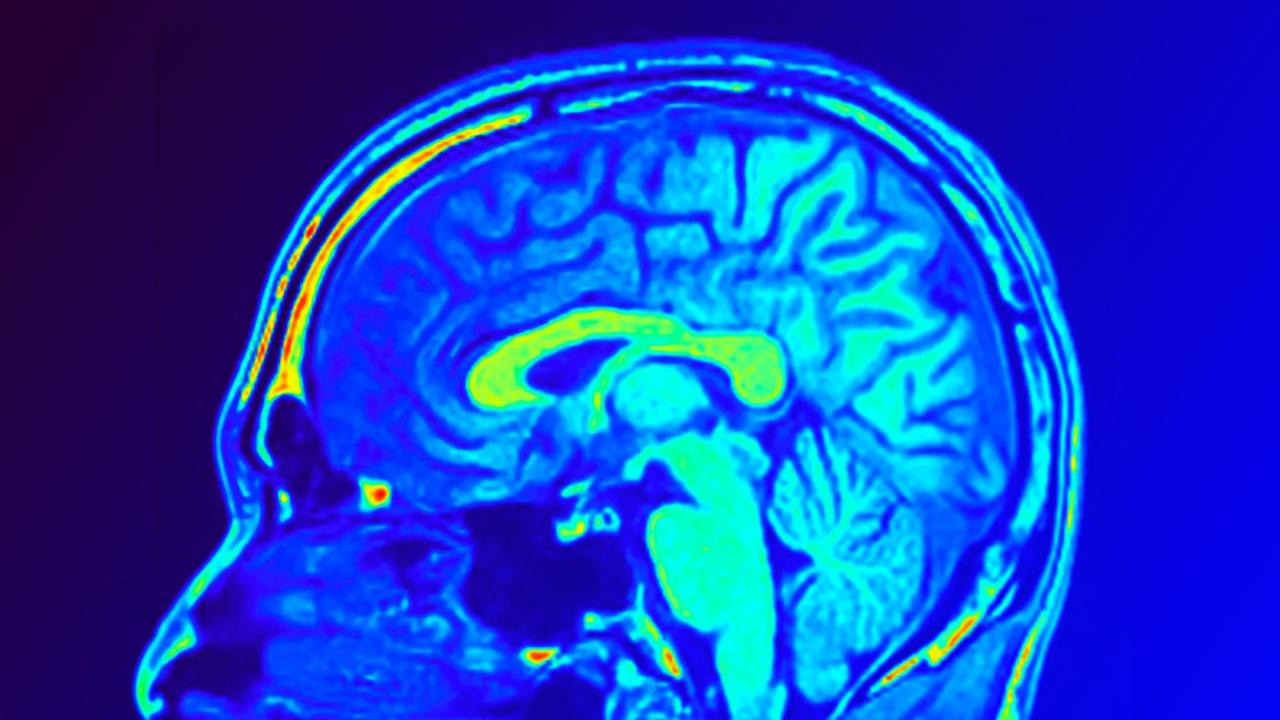

Az agyi MRI új korszakot nyithat a depresszió gyógyításában

Egy új kutatás során kínai kutatók 28 depressziós pácienst vontak be egy randomizált, kettős vak, placebo-kontrollált vizsgálatba a taizhoui Központi Kórházban. Az egyik csoport a Yueju nevű hagyományos gyógynövényt kapta, míg a másik a világszerte elterjedt escitalopram nevű antidepresszánst. Mindkét csoport placebót is szedett a másik készítmény helyett, így a vizsgálat torzításmentes maradt. A depresszió súlyosságát a Hamilton-skála (HAMD-24) alapján értékelték, emellett vért vettek és MRI-vel vizsgálták az agy szerkezetét.

Mindkét kezelés javulást eredményezett, vagyis a Yueju és az escitalopram egyformán hatékonynak bizonyult a tünetek enyhítésében. Mégis akadt egy kiemelkedő különbség: a Yueju csoportnál jelentősen emelkedett a BDNF nevű agyi fehérje szintje, amelyet korábban már összefüggésbe hoztak a depresszióval és az idegsejtek egészségével. Az MRI-felvételek további érdekességekre világítottak rá: bizonyos agyi hálózatok elrendeződése előre jelezte, hogyan alakulnak a depressziós tünetek mindkét csoportban. A Yueju csoportnál emellett olyan mintázatokat is találtak (például az agykéreg vastagsága és barázdáinak mélysége alapján), amelyek előre jelezték a kezelés eredményességét, főként a vizuális hálózatokban.

Összességében a modern agyi képalkotó eljárások és a hagyományos gyógymódok kombinációja új lehetőségeket nyithat a személyre szabott depresszióterápiában. Ha nagyobb minta mellett is beigazolódnak az eredmények, a jövőben az orvosok MRI-alapú modellek segítségével előre tudják majd jelezni, kinél melyik kezelés válik be, jelentősen csökkentve a próbálkozásos terápiák idejét.